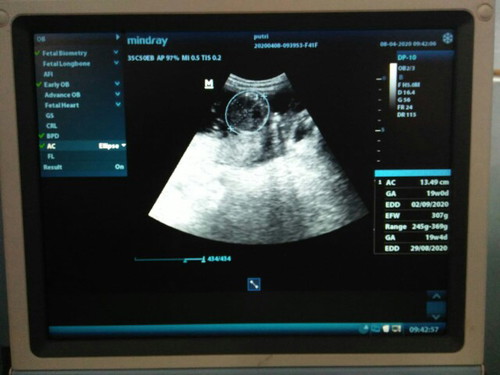

hasil usg

Mohon penjelasannya dong bund, soalnya kemeren bidannya ngak terlalu jelas menjelaskan hasil USG nya bun , kata bidan sdh hamil ke 19w tpi perut saya msh sangat kecil dan tdk mnglmi perubahan fisik bun ...

Iyah itu d ukur lingkar perutnya usia kehamilan 19week berat janin 307gram HPL sekitar bulan 8